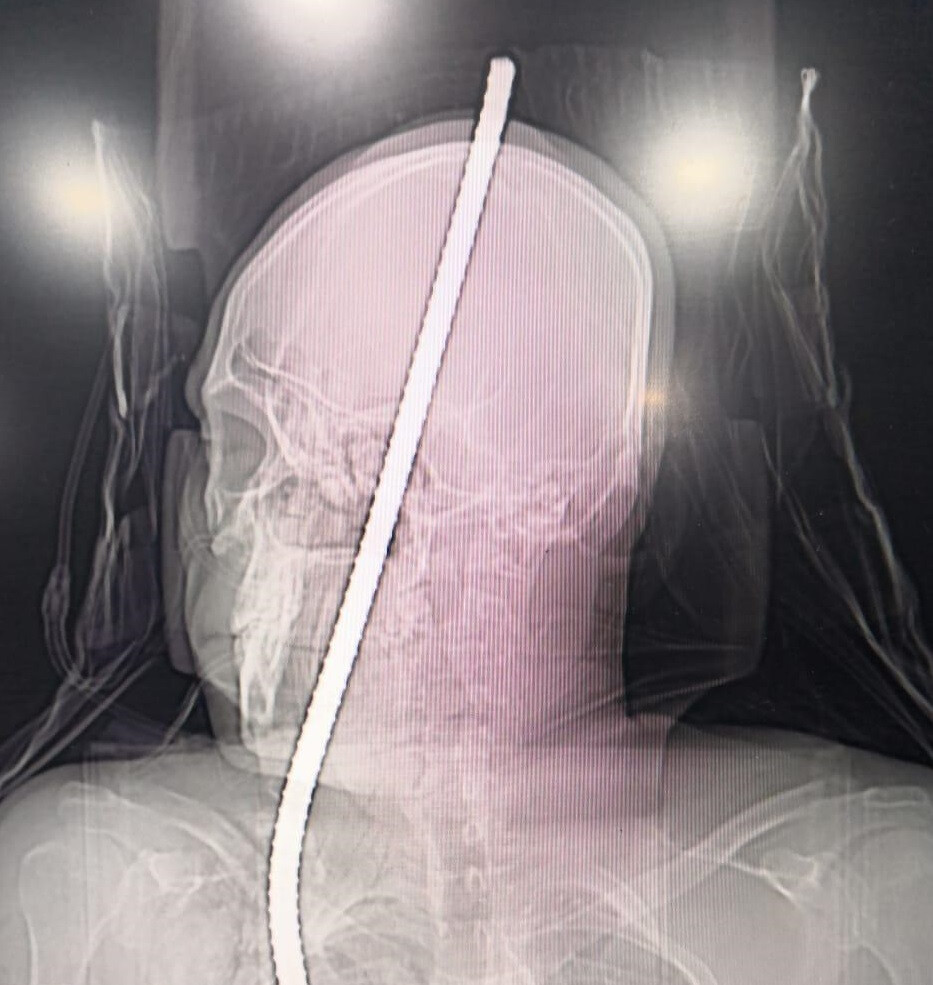

मंगळवारी २० नोव्हेंबर रोजी चेंबूरजवळील उंच इमारतीचं बांधकाम सुरू असताना अचानक १३ फुटांवरून तोल जाऊन राकेश जाधव खाली पडला. तोल गेलेल्या राकेशच्या छातीत ३ फूट लोखंडी सळी घुसली व ती थेट त्याच्या डोक्यातून बाहेर पडली. बराच रक्तस्त्राव झाल्यानं त्याला वाचवणं अशक्य होतं. परंतु प्रसंगावधान राखून काही कामगारांनी राकेशला जवळच्या झेन रुग्णालयात दाखल केलं.

रुग्णालयात दाखल करण्यात आल्यानंतर झेन रुग्णालयातील न्युरोसर्जन डॉ. बटुक डिओरा, डॉ. प्रमोद मस्जीद, डॉ. प्रमोद काळे यांसह इतर डॉक्टरांच्या मदतीन त्याच्यावर शस्त्रक्रिया करण्यात आली. ५ तासाच्या गुंतागुंतीच्या शस्त्रक्रियेनंतर त्याच्या छातीत घुसलेली लोखंडी सळी काढण्यात आली. ही शस्त्रक्रिया यशस्वी झाल्यानं राकेशचा जीव वाचवण्यात रूग्णालय प्रशासनाला यश आलं.